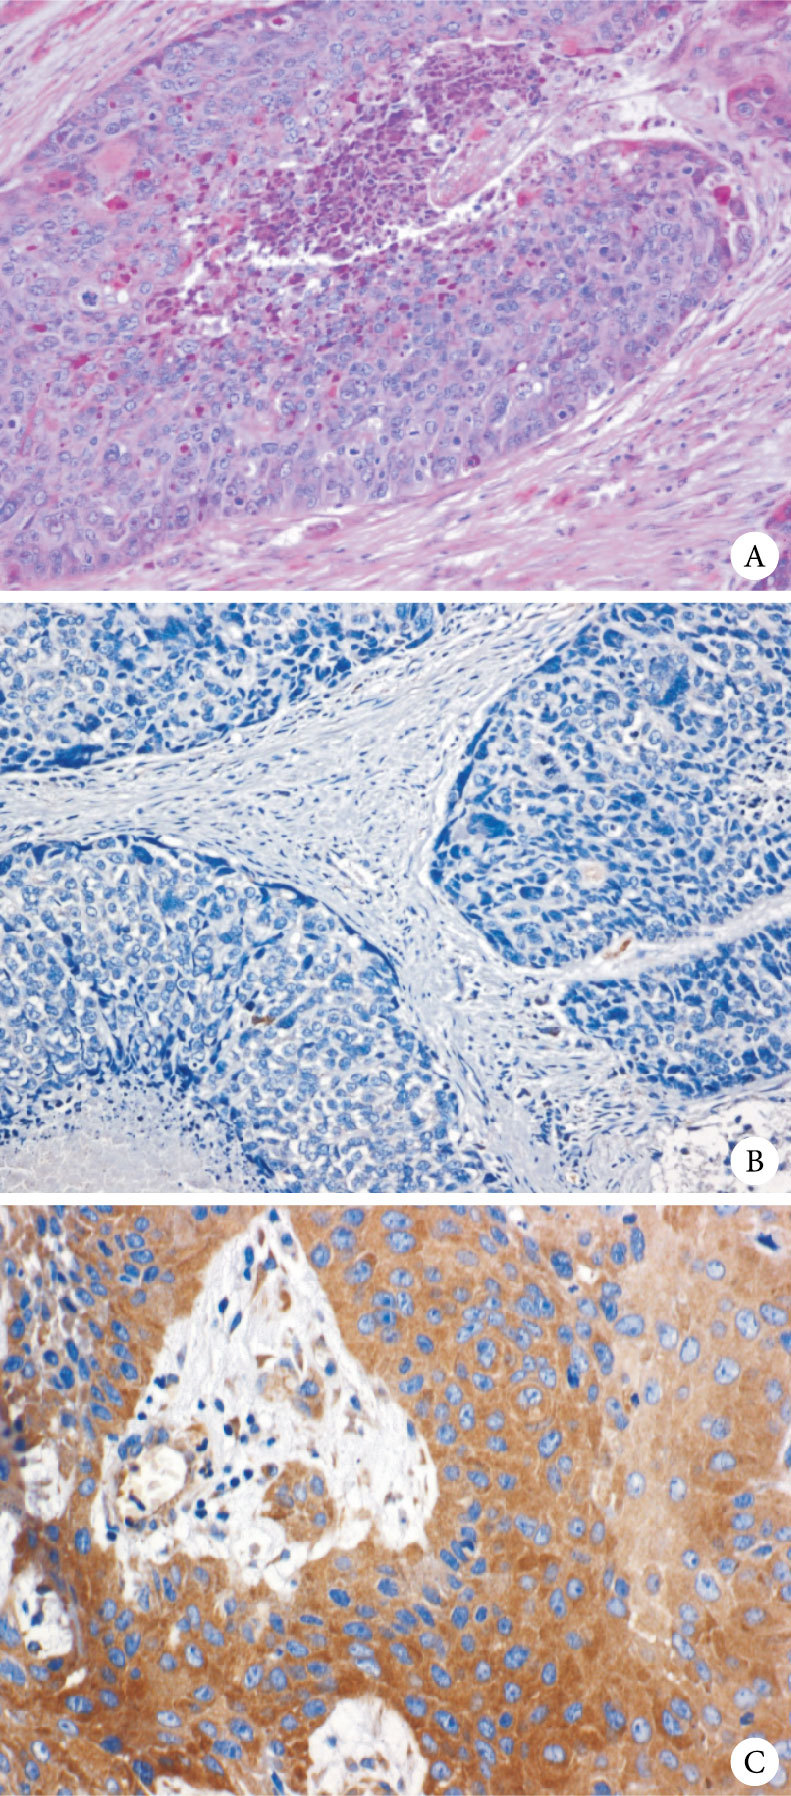

在72例維吾爾族患者食管鱗癌組織中VEGFR-2陽性表達率為80.56% (58/72)(圖 1),相應的28例維吾爾族食管鱗癌患者癌旁正常組織VEGFR-2均無陽性表達(0/28);兩組差異有統計學意義(P<0.05,表 1)。

注:A為中分化鱗狀細胞癌 HE ×20;B為VEGFR-2陰性表達,中分化鱗狀細胞癌免疫組織化學SP法 ×20;C為VEGFR-2陽性表達,中-高分化鱗狀細胞癌免疫組織化學SP法 ×20